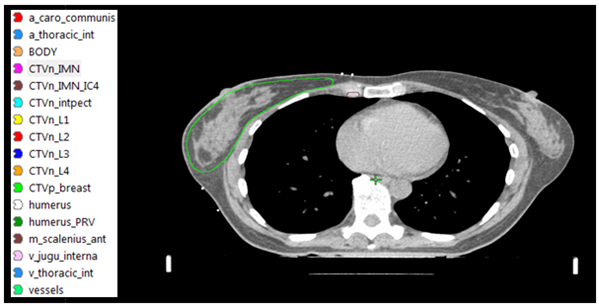

Figur 2. CTV enligt ESTRO consensus guideline [4]. Targetvolymen innehåller all bröstkörtelvävnad. Röntgentät tråd kan användas vid CT-undersökningen för att markera kvarvarande bröst, ärr efter sektorresektion/mastektomi eller området där bröstet suttit efter mastektomi.

Figur 3. CTVN enligt ESTRO consenus guideline [4]. Inritningen av lymfkörtelvolymerna underlättas genom att vissa landmärken i form av vener och artärer definieras.